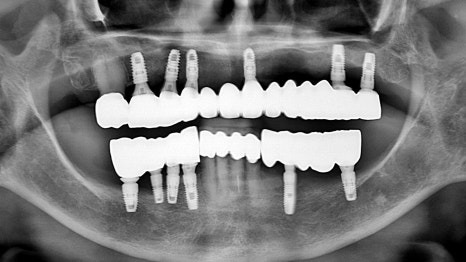

수술 전 CT 영상을 분석한 결과

위 파노라마 사진에 빨간 표시된 부분은

치조골(잇몸뼈)이 오랜 시간 너무 퇴축되어서

임플란트 식립이 불가능했습니다.

광범위한 뼈 이식 수술은

환자분의 체력과 여건 상 힘들었기에

파란 표시된 부분에만 임플란트를 식립하여

최소한의 수술로 최적의 결과를

낼 수 있도록 고민하였습니다.

임플란트는 추가로 4개만 식립하여

비용과 시간, 위험성, 부작용 등을

모두 감소시키기로 하였고,